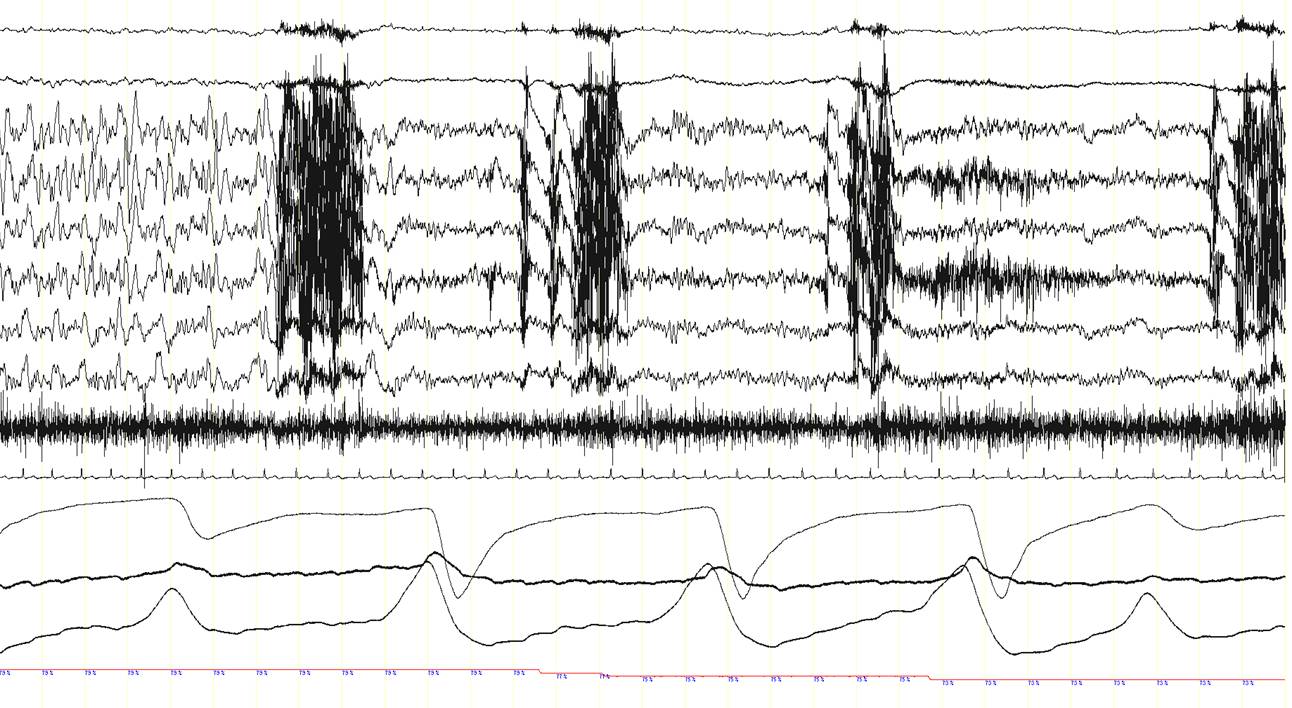

A 63 year-old man was diagnosed with obstructive sleep apnea syndrome because of habitual heavy snoring with breathing pauses during sleep, occasional awakenings and mild excessive daytime somnolence. The patient also complained of recurrent episodes of sudden dizziness, pallor, sweating, and sometimes pain in the right shoulder, either awake or during sleep. An electroencephalography (EEG), brain CT scan and cardiac exercise stress test revealed normal findings and the nature of these episodes had remained elusive. A baseline polysomnographic (PSG) study showed frequent obstructive sleep apneas, particularly in the supine position (apnea-hypopnea index in this position: 33/hour; not shown here). A subsequent continuous positive airway pressure (CPAP) titration PSG study was performed. With a CPAP pressure of 7 cm H2O obstructive events were well-controlled. Suddenly, however, the patient presented an apnea (panel A, between arrows) with a change in the EEG signals. This is shown in the three consecutive 30-second epochs (panel A, B and C). In panel D, a 20-second epoch of the event is shown. Can you describe what is happening here?

Note the presence of epileptogenic activity on the EEG channels just after the onset of the central apnea while the patient is in NREM sleep (N2). A rhythmic 8-9 Hz EEG activity is recorded in the left frontal area (red arrow, F3-REF), which rapidly spreads over the rest of the hemisphere and to the contralateral side (green arrow), and progressively increases in amplitude and decreases in frequency to theta (4-5 Hz) and finally delta ranges (2-3 Hz) (blue arrows). This ictal EEG rhythmic activity lasted approximately 1 minute (end of the ictal rhythm: red arrow in the third epoch; panel C). Remarkably, during this seizure with an initial ictal central apnea, oxyhemoglobin saturation dropped to 73%. The patient also presented repetitive chewing movements (see the artefact caused by masticatory movements in the EEG channels; red asterisks), but overt convulsions or other abnormal movements or behaviours were not recorded. The patient was unaware of this seizure and did not recall any event during the night the following morning.